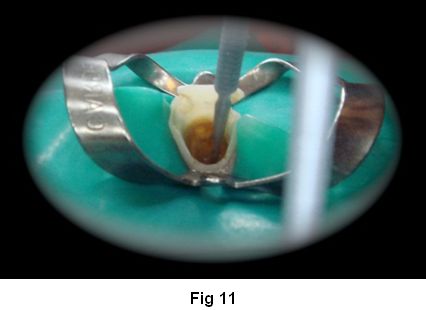

6. Lubricamos en conducto con glicerina líquida (sustancia hidrosoluble) (Fig. 11)